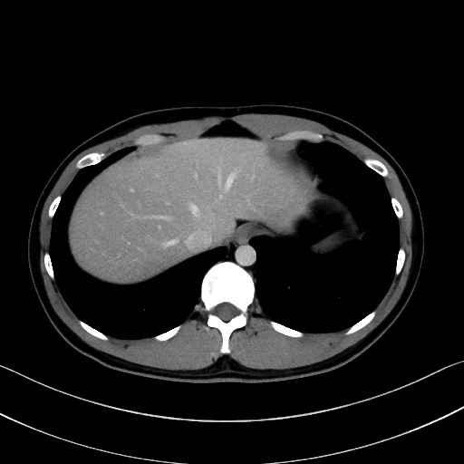

腰方形筋 (Quadratus lumborum)